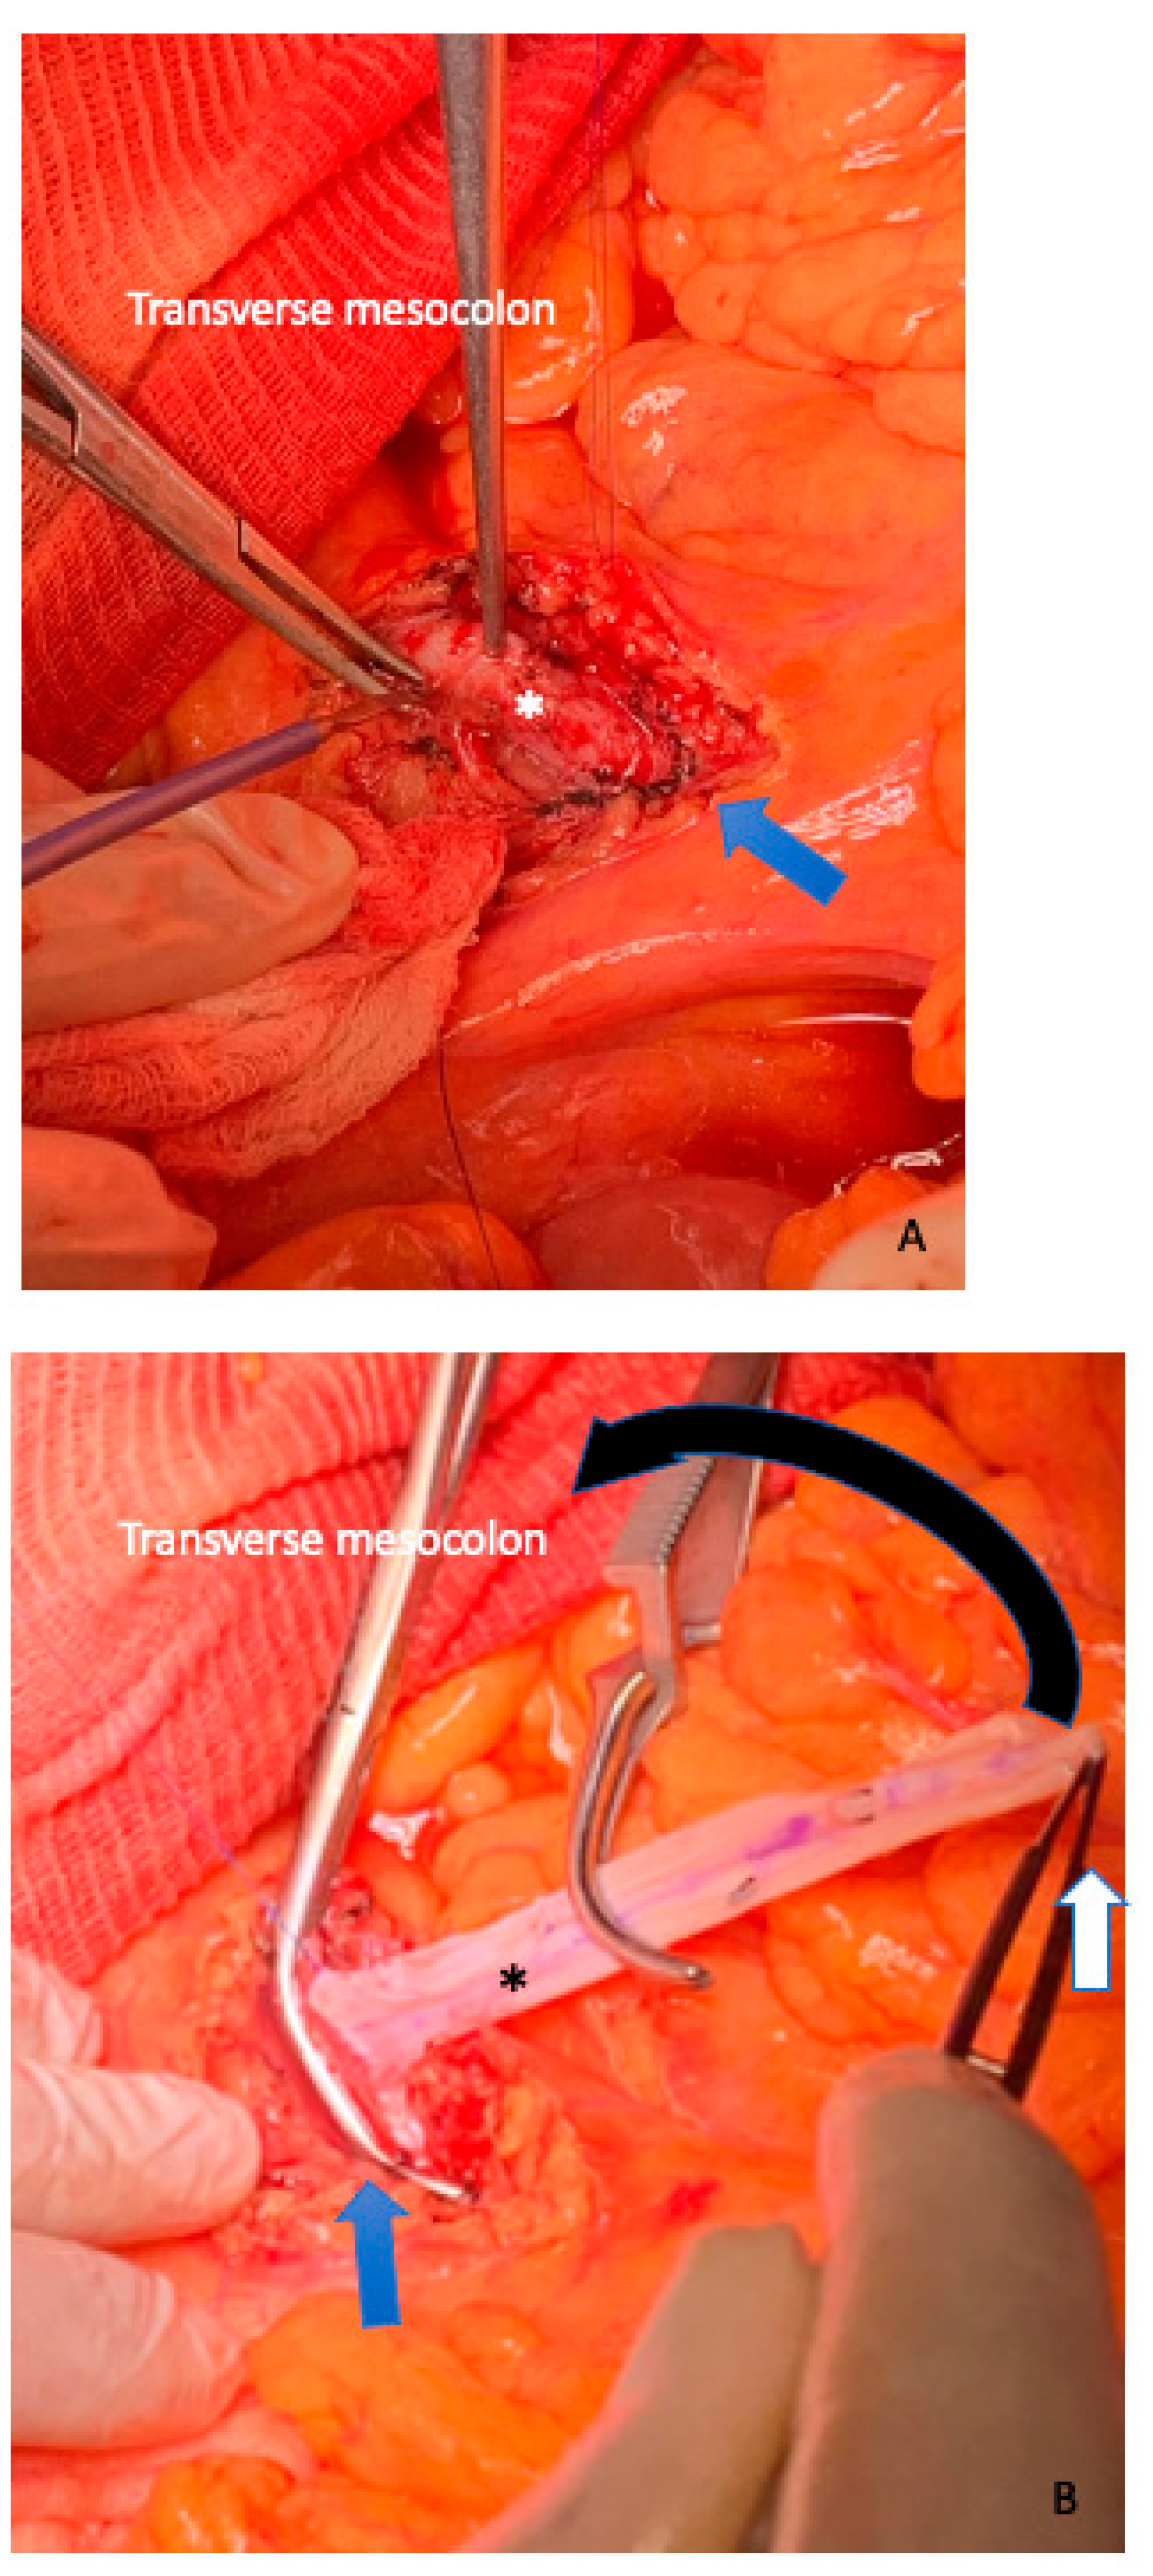

5. Vein Resection and Reconstruction

6. Arterial Resection